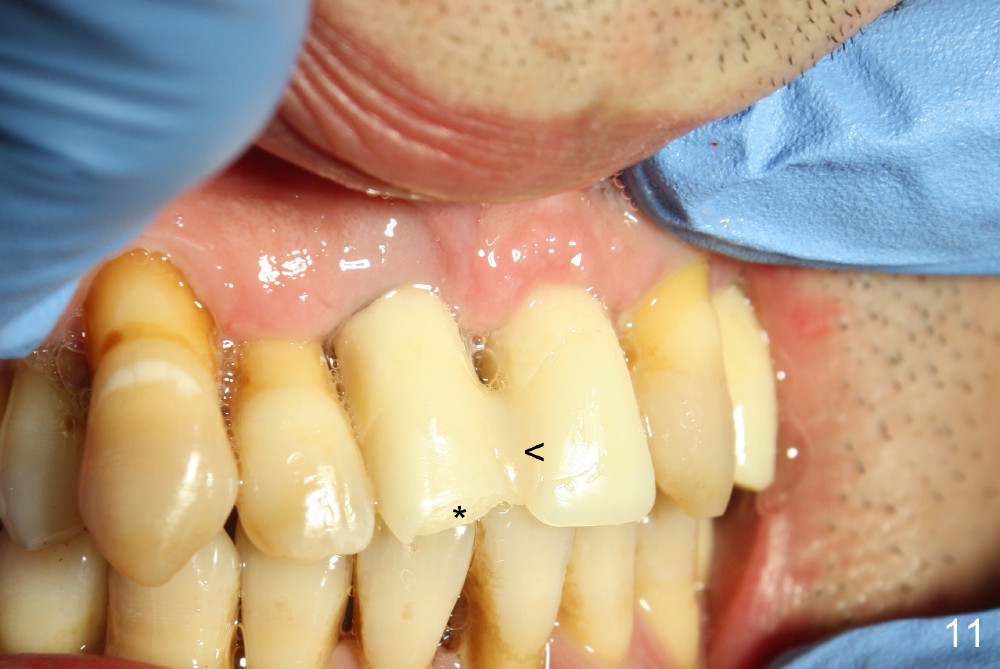

These two anterior implants remain stable 2 months 20 days postop, since one of the immediate provisionals has incisal chip (Fig.11 *) while both of them are splinted (<) to increase retention. There is no complain about paresthesia around the incisal papilla due to separation of the nasopalatine nerve. Mesiodens sockets disappear 7 months postop (Fig.13). There is no bone loss 2 years 9 months postop (Fig.14 panoramus) or 4 years 10 months postop (Fig.15,16 CT). The buccal gingiva is reddish and swollen with bleed on probing and history of pain 7 years post cementation (Fig.17). There is no bone loss in PA (Fig.18). The buccal plate at #9 is thinner than that at #8 4 years 10 months post cementation (Fig.19,20).